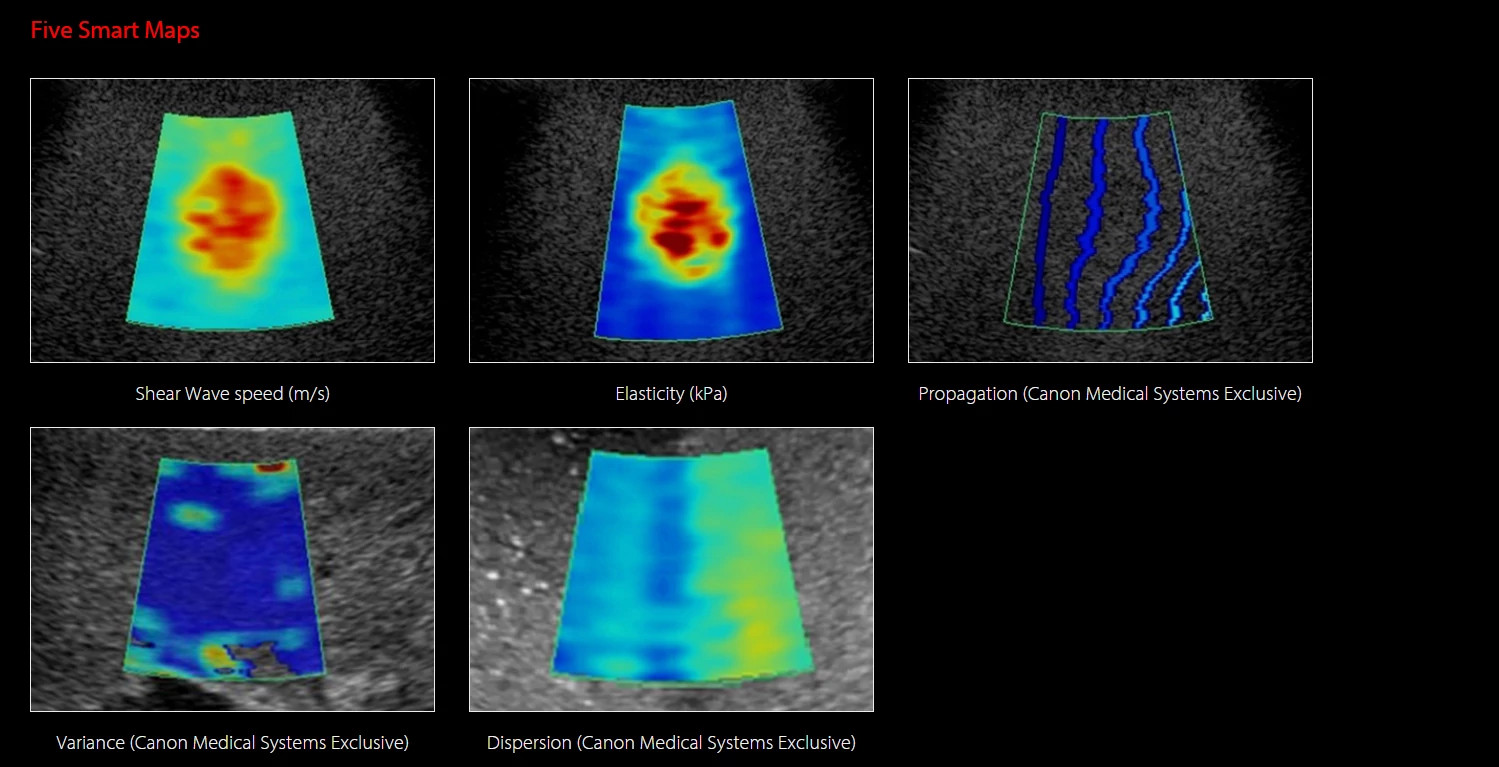

A megbízható diagnózis érdekében a Canon olyan új és egyedi képalkotó eszközöket fejlesztett, amelyek képesek láthatóvá tenni a májszövet állapotában bekövetkező változásokat.

A diagnosztikus bizonyosság érdekében a Canon új és egyedi képalkotó technológiákat fejlesztett,

melyek a májállapot változásainak vizuális és kvantitatív megjelenítését teszik lehetővé.

A Canon Shear Wave technológiája kvantitatív és dinamikus vizuális információt nyújt a szöveti merevségről különböző klinikai környezetekben.

Multi-Parametric Report - Integrált jelentés májalkalmazásokhoz

A multiparametrikus jelentés képes egyesíteni az ultrahangos és külső vizsgálatok (pl. laboreredmények) adatait, hogy átfogóbb képet adjon a máj állapotáról.

Az eredmények táblázatos formában vagy pókháló (spider) diagramon is megjeleníthetők, ahol a vizuális mintázat segíti az eredmények közötti összefüggések értelmezését.

A jelentés kombinálható a következő modulok eredményeivel:

Shear Wave Elastography

Shear Wave Dispersion Map

Attenuation Imaging